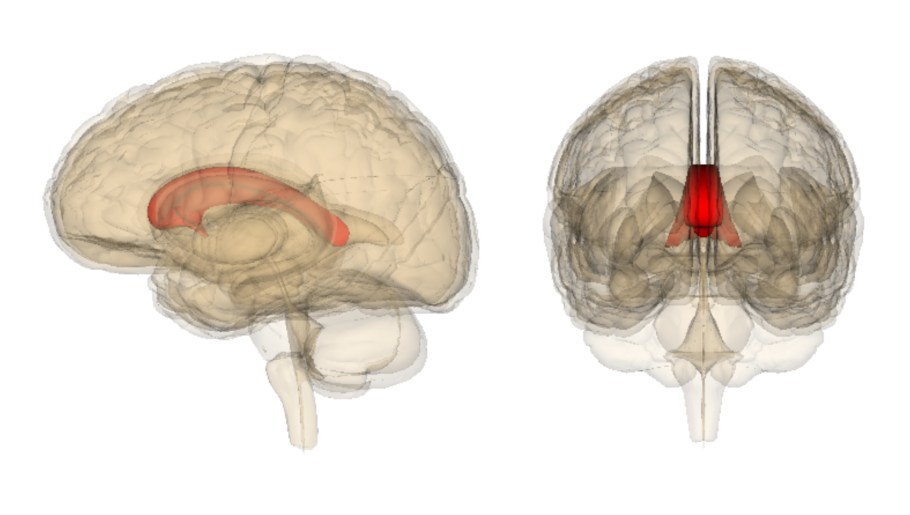

Каллозотомия мозолистого тела

Комиссуральные волокна головного мозга

Мозолистое тело человека